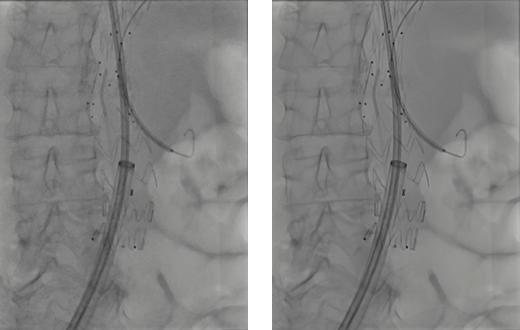

“ARTIS pheno.vision”专为混合手术室设计,搭载了OPTIQ AI图像处理技术。通过该AI技术,图像生成过程中噪声得以大幅抑制,能够获得高精细度和高对比度的图像。

此外,利用AI驱动的高级算法,在二维透视和拍摄模式及多种部位中,实时降低量子噪声和电子噪声的同时保持信号强度。这样可以清晰显示细小血管、导管和导丝等治疗设备,确保良好的视觉识别效果。

借助AI技术获得的清晰图像,不仅提升了操作性和诊疗质量,还能在远低于诊断参考剂量的辐射水平下进行检查和治疗,有效减少患者及医护人员的辐射暴露。